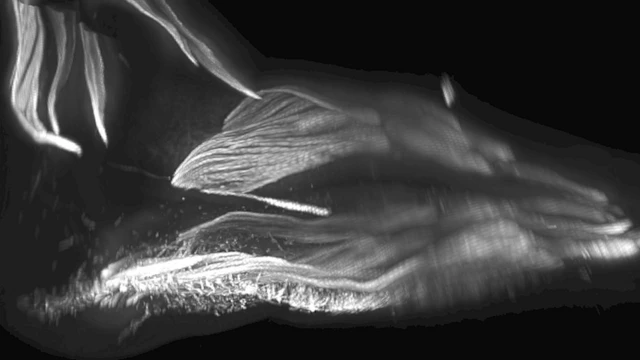

Bilim insanları embriyoların ayaklarını gözlemlediğinde de bazı kasların önce oluşup sonra yok olduğunu keşfetmişlerdi.

Bu kaslar, maymunların ağaçlara tırmanmak ve nesneleri ayaklarıyla kontrol etmek için kullandığı kaslardı.